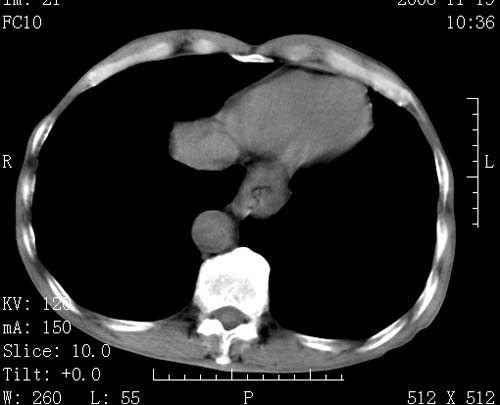

标题: CT16691:m 67 胃镜确诊食管下段及贲门癌 [打印本页]

标题: CT16691:m 67 胃镜确诊食管下段及贲门癌

术前查体,双肺部结节是转移?结核?请点评

转移 隆突下淋巴结亦肿大

首先考虑转移,纵隔内淋巴结亦肿大;

1)符合食管癌表现。2)两肺及纵隔淋巴结多发性转移瘤。3)左肺上叶舌段及两肺下叶炎症感染。

食管癌伴双肺转移,评述:肺部毛细血管网丰富,全身血液均快速流经肺部,癌细胞容易过滤定植,形成转移瘤,影象特点为以毛细血管末梢为中心的结节灶,边缘光滑锐利,少见有中心空洞着,不同来源的转移瘤可有各自特点,如甲状腺癌为双肺弥漫性微结节,本例有原发灶,双肺影象灶典型,左肺舌段条带状网格样伴胸膜天幕征,可视为癌性淋巴管炎。